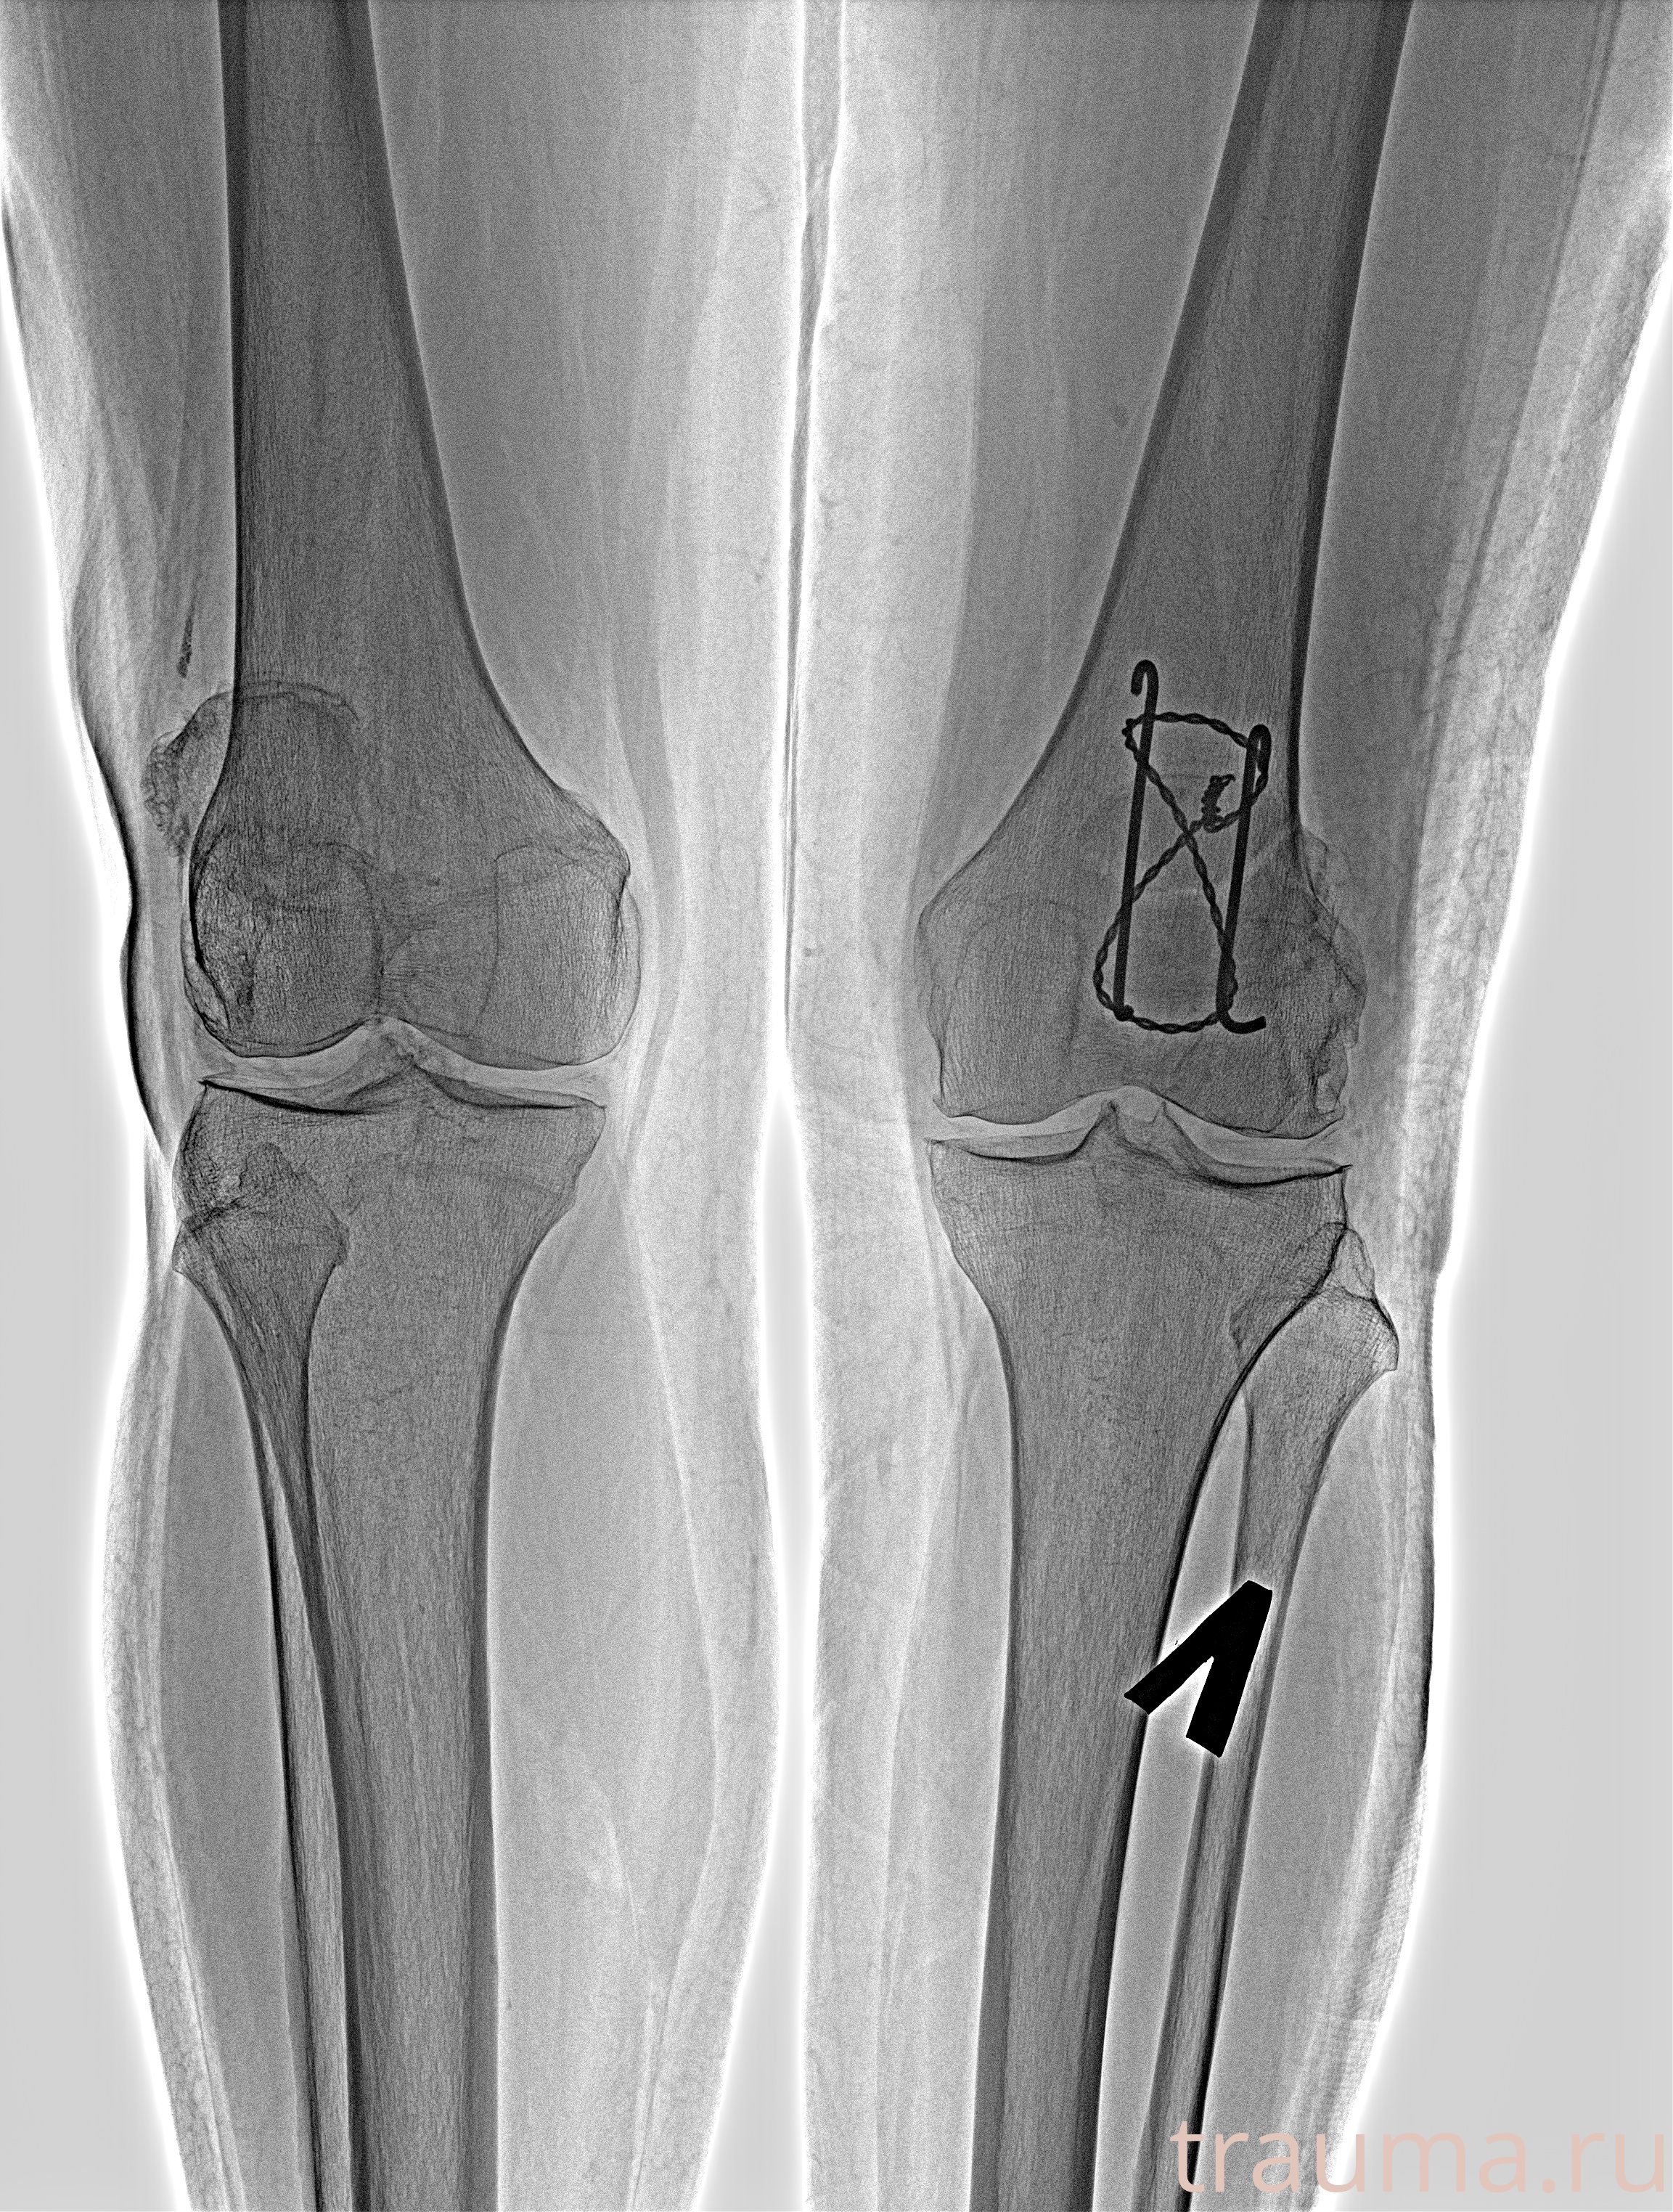

Рентгенограммы

Яркость: 1   Контраст: 1   Инвертировать: 0 Увеличение: 1

Перетаскивайте мышь вверх/вниз для контраста, влево/право для яркости. Прокрутка колесом изменяет масштаб. Нажмите Сбросить для возврата к исходному изображению. При увеличении держите мышь в той области, которую хотите рассмотреть.